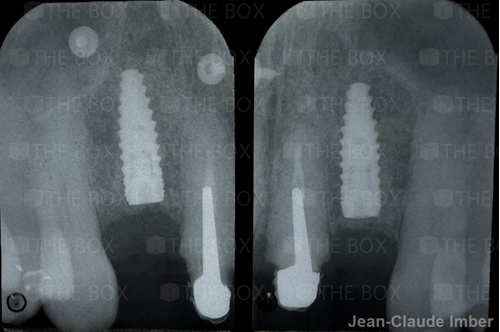

ELSAID Ahmed

Infra bony defect one wall defect follow up 18 months show regeneration of buccal bone and interdental defect utilizing allograft bone substitute